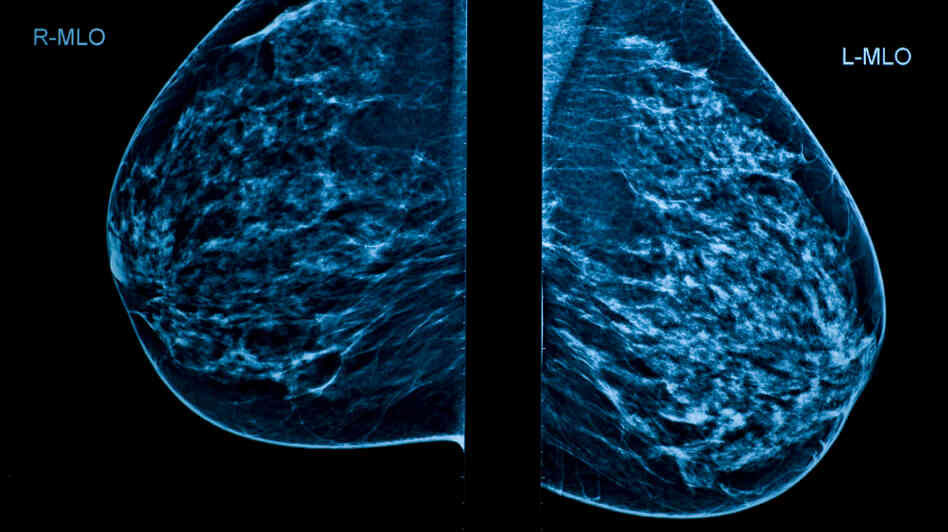

hide captionMammograms are a key screening tool for breast cancer. But critics say they're not good enough.

Mammograms don't reduce the number of women dying from breast cancer, according to a large and long-term Canadian study. It's the latest chunk of data to raise questions in an increasingly partisan debate about the use of mammograms to screen for cancer.

Improvements in breast cancer treatment since the study began in 1980 have reduced the importance of mammograms in saving lives, according to the study, which was published Tuesday in the British journal BMJ. The study involving almost 90,000 women found no difference in death rates between those who had mammograms and those who had annual physical exams performed by trained nurses.

The study also suggested that breast cancer is being overdiagnosed, with about 1 in 5 cancers found through screening mammography turning out to be a kind that would have posed no lethal threat if the cases hadn't been found.

But because there's currently no way of knowing for sure which breast cancers will become life-threatening, all the cancers end up being treated. Other studies have come up with similar estimates for overdiagnosis.